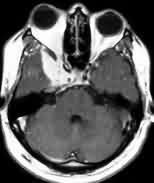

|

Bifalcine

meningioma-MRI

|

Falx meningioma-MRI